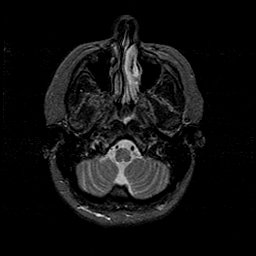

MR Study #1 -- Slice #10

[Home][Help][Clinical][Tour 1][Tour 2][Tour 3] Slice 10